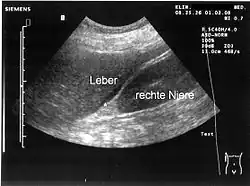

- Sonografie (Ultraschall): Geringe Mengen von Aszites lassen sich dabei am ehesten am Unterrand der Leber oder knapp oberhalb der Harnblase nachweisen. Der Raum zwischen Leber und Niere (Morison-Grube oder Recessus hepatorenalis) ist im Liegen der tiefste Punkt des Oberbauchs.